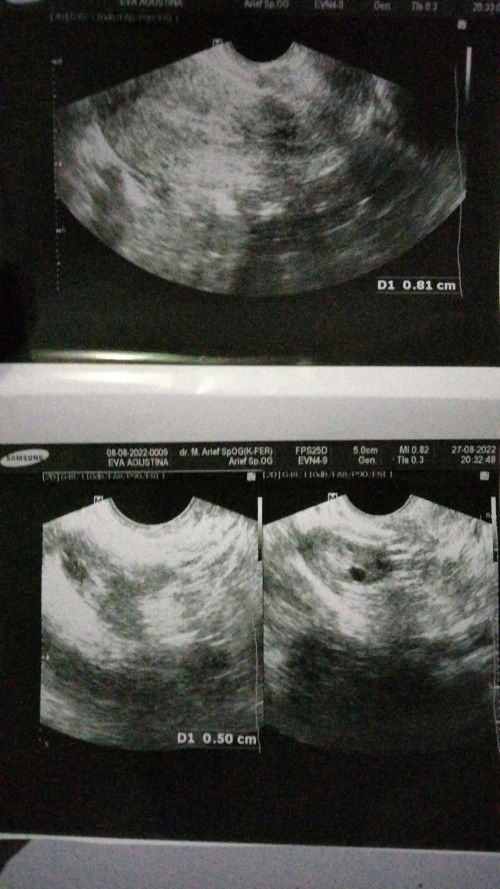

Bunda, saya mengalami flek 3 hr, ternyata dinding rahim saya sudah TDK ada 😭😭 ini kehamilan saya yg ke 2x nya 😭kehamilan pertama saya THN 2019 mengalami secar karena janin berkembang bukan ditempatnya, jd sel telur saya diambil 1 sebelah kiri, skrg hamil yg ke 2 di usia 7w itu cuma sel telurnya 1 dan saya masih penebalan dinding rahim, pas usia 8w trus sy mengalami flek, pas usg kemaren, dokter bilang dinding rahim saya sudah ga ada 😭😭😭😭 ya Allah Bun.. doain saya ya 😭😭🙏🙏